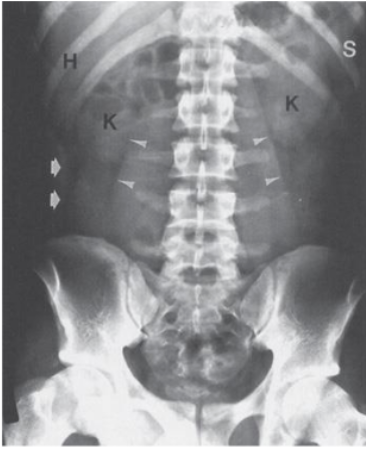

What are H, S, K what type of scan is this

H: Hepatic angle, S: spleen, K: kidney, Normal Abdominal X-ray